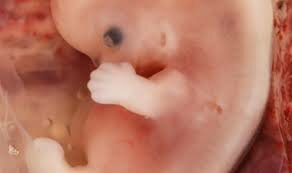

• Period: to

Weeks 7/8

The brain and face begin to grow. The 4 chamber heart- lungs begin to form. Fingers and toes being to form.